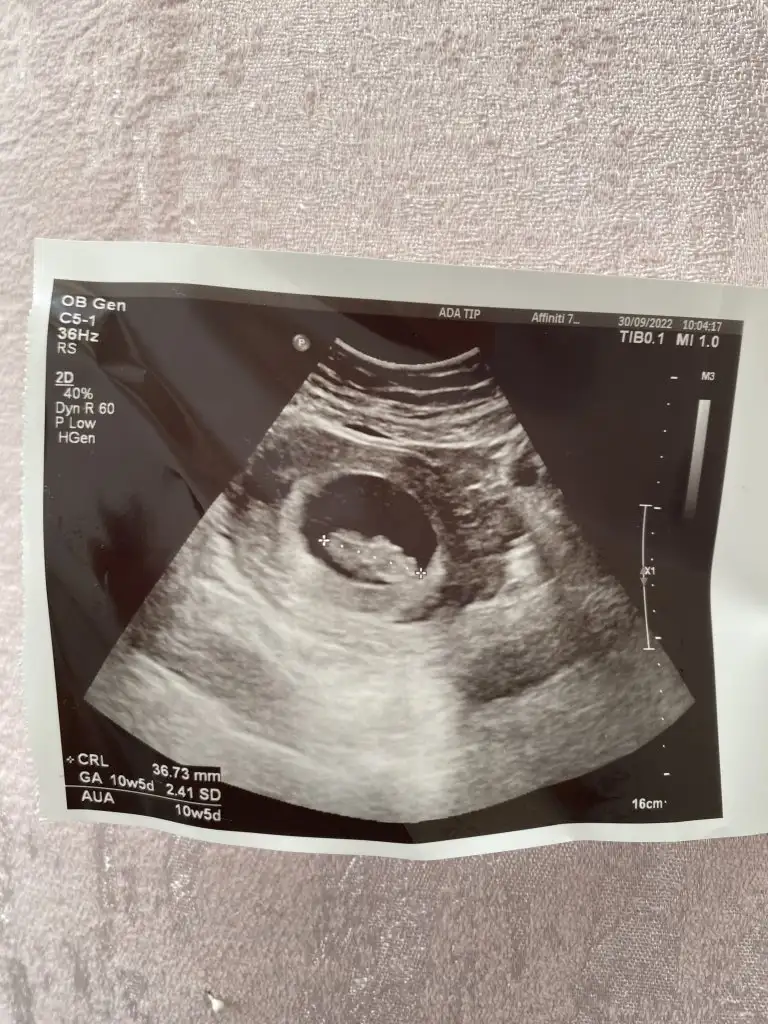

Bebek kesenin sağında mi gorunmuyo plesanta sanki ordaMerhaba banada yorum yaparmısınız 5+4 karından ultrason

Ramziye göre bana da yorum yapar mısınız hiç anlamadım nasıl olduğunu. 5 haftalık karından çekildiOlabilir ramzide doğru cikiyo ramziyegore erkek yarın ogrenirseniZ yazın bnde yarın ogrenecem beraber yazalım bnm ramziye göre erkek sizinde erkek bakalim m doğru çıkacak mi

İnanın artık bilmiyorum bnm erkektiramziye göre kız olduğunu ogrendimRamziye göre bana da yorum yapar mısınız hiç anlamadım nasıl olduğunu. 5 haftalık karından çekildi